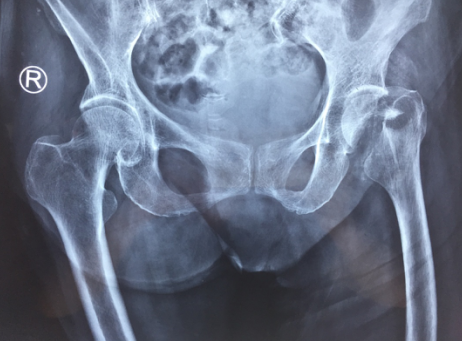

术前

术后

手术按照术前计划顺利进行,仅用了50分钟,手术小组就完成了汤奶奶的左人工股骨头置换手术。手术后,情况良好的老人被直接送回关节病区康复,此后,老人的康复速度很快,精神状态一天比一天好,第二天就能下地行走,仅一周时间就出院了。